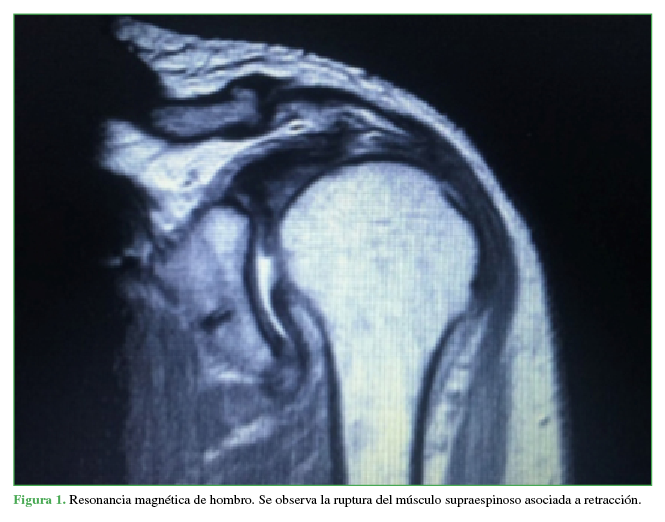

Traumatic injury of the axillary nerve identified after rotator cuff repair